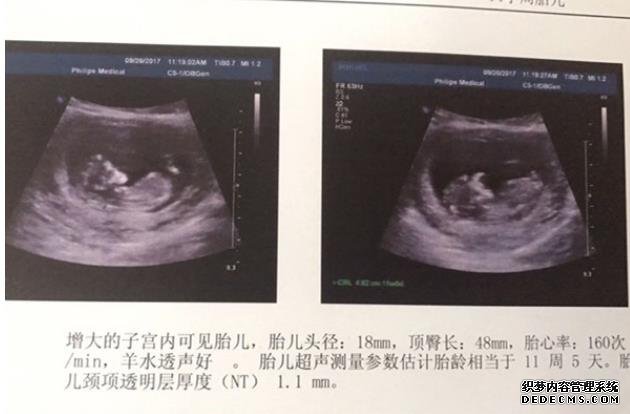

绝经女人怀孕指的是45岁及以上的女性出现了...